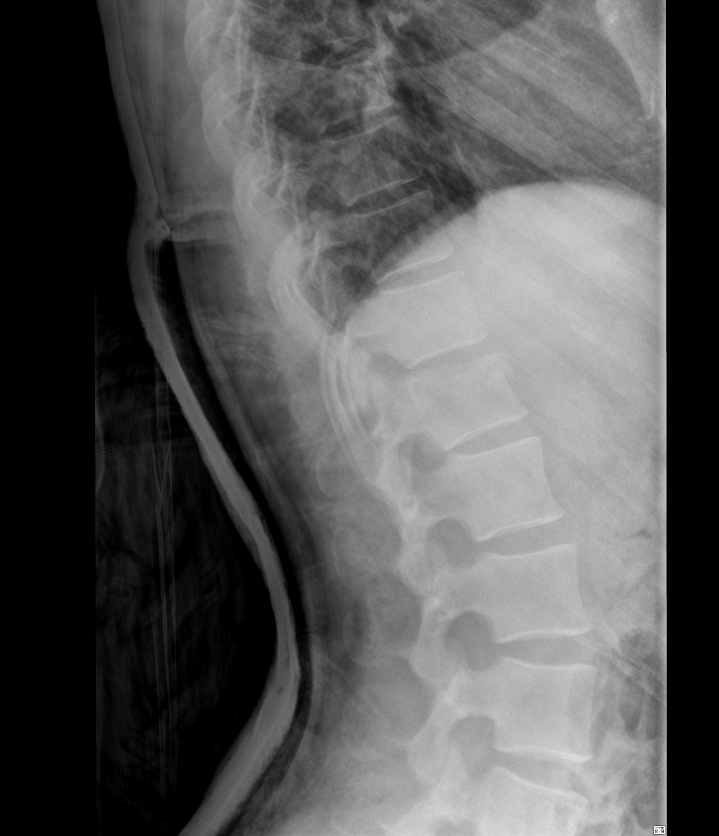

2. 척추 압박률 확인

다행히 수술할 정도가 아니라면 척추압박률을 확인해야 하는데요.

압박률은 골절된 척추를 기준으로 윗 척추의 길이와 아래척추의 길이를 구해서 평균을 낸 후

골절된 척추의 길이로 나누면 산출되는데

사진에서 보는 것처럼 척추는 사다리꼴 형태로 눌리기 때문에

어느 지점에서 길이를 재느냐에 따라 압박률이 달라집니다.

그리고 어느지점에서 길이를 재는지의 문제는

명시된 지침이 없기 때문에 의사의 고유권한이구요.

그래서 같은 척추골절에도 병원마다 압박률에 차이가 있을수 밖에 없습니다.